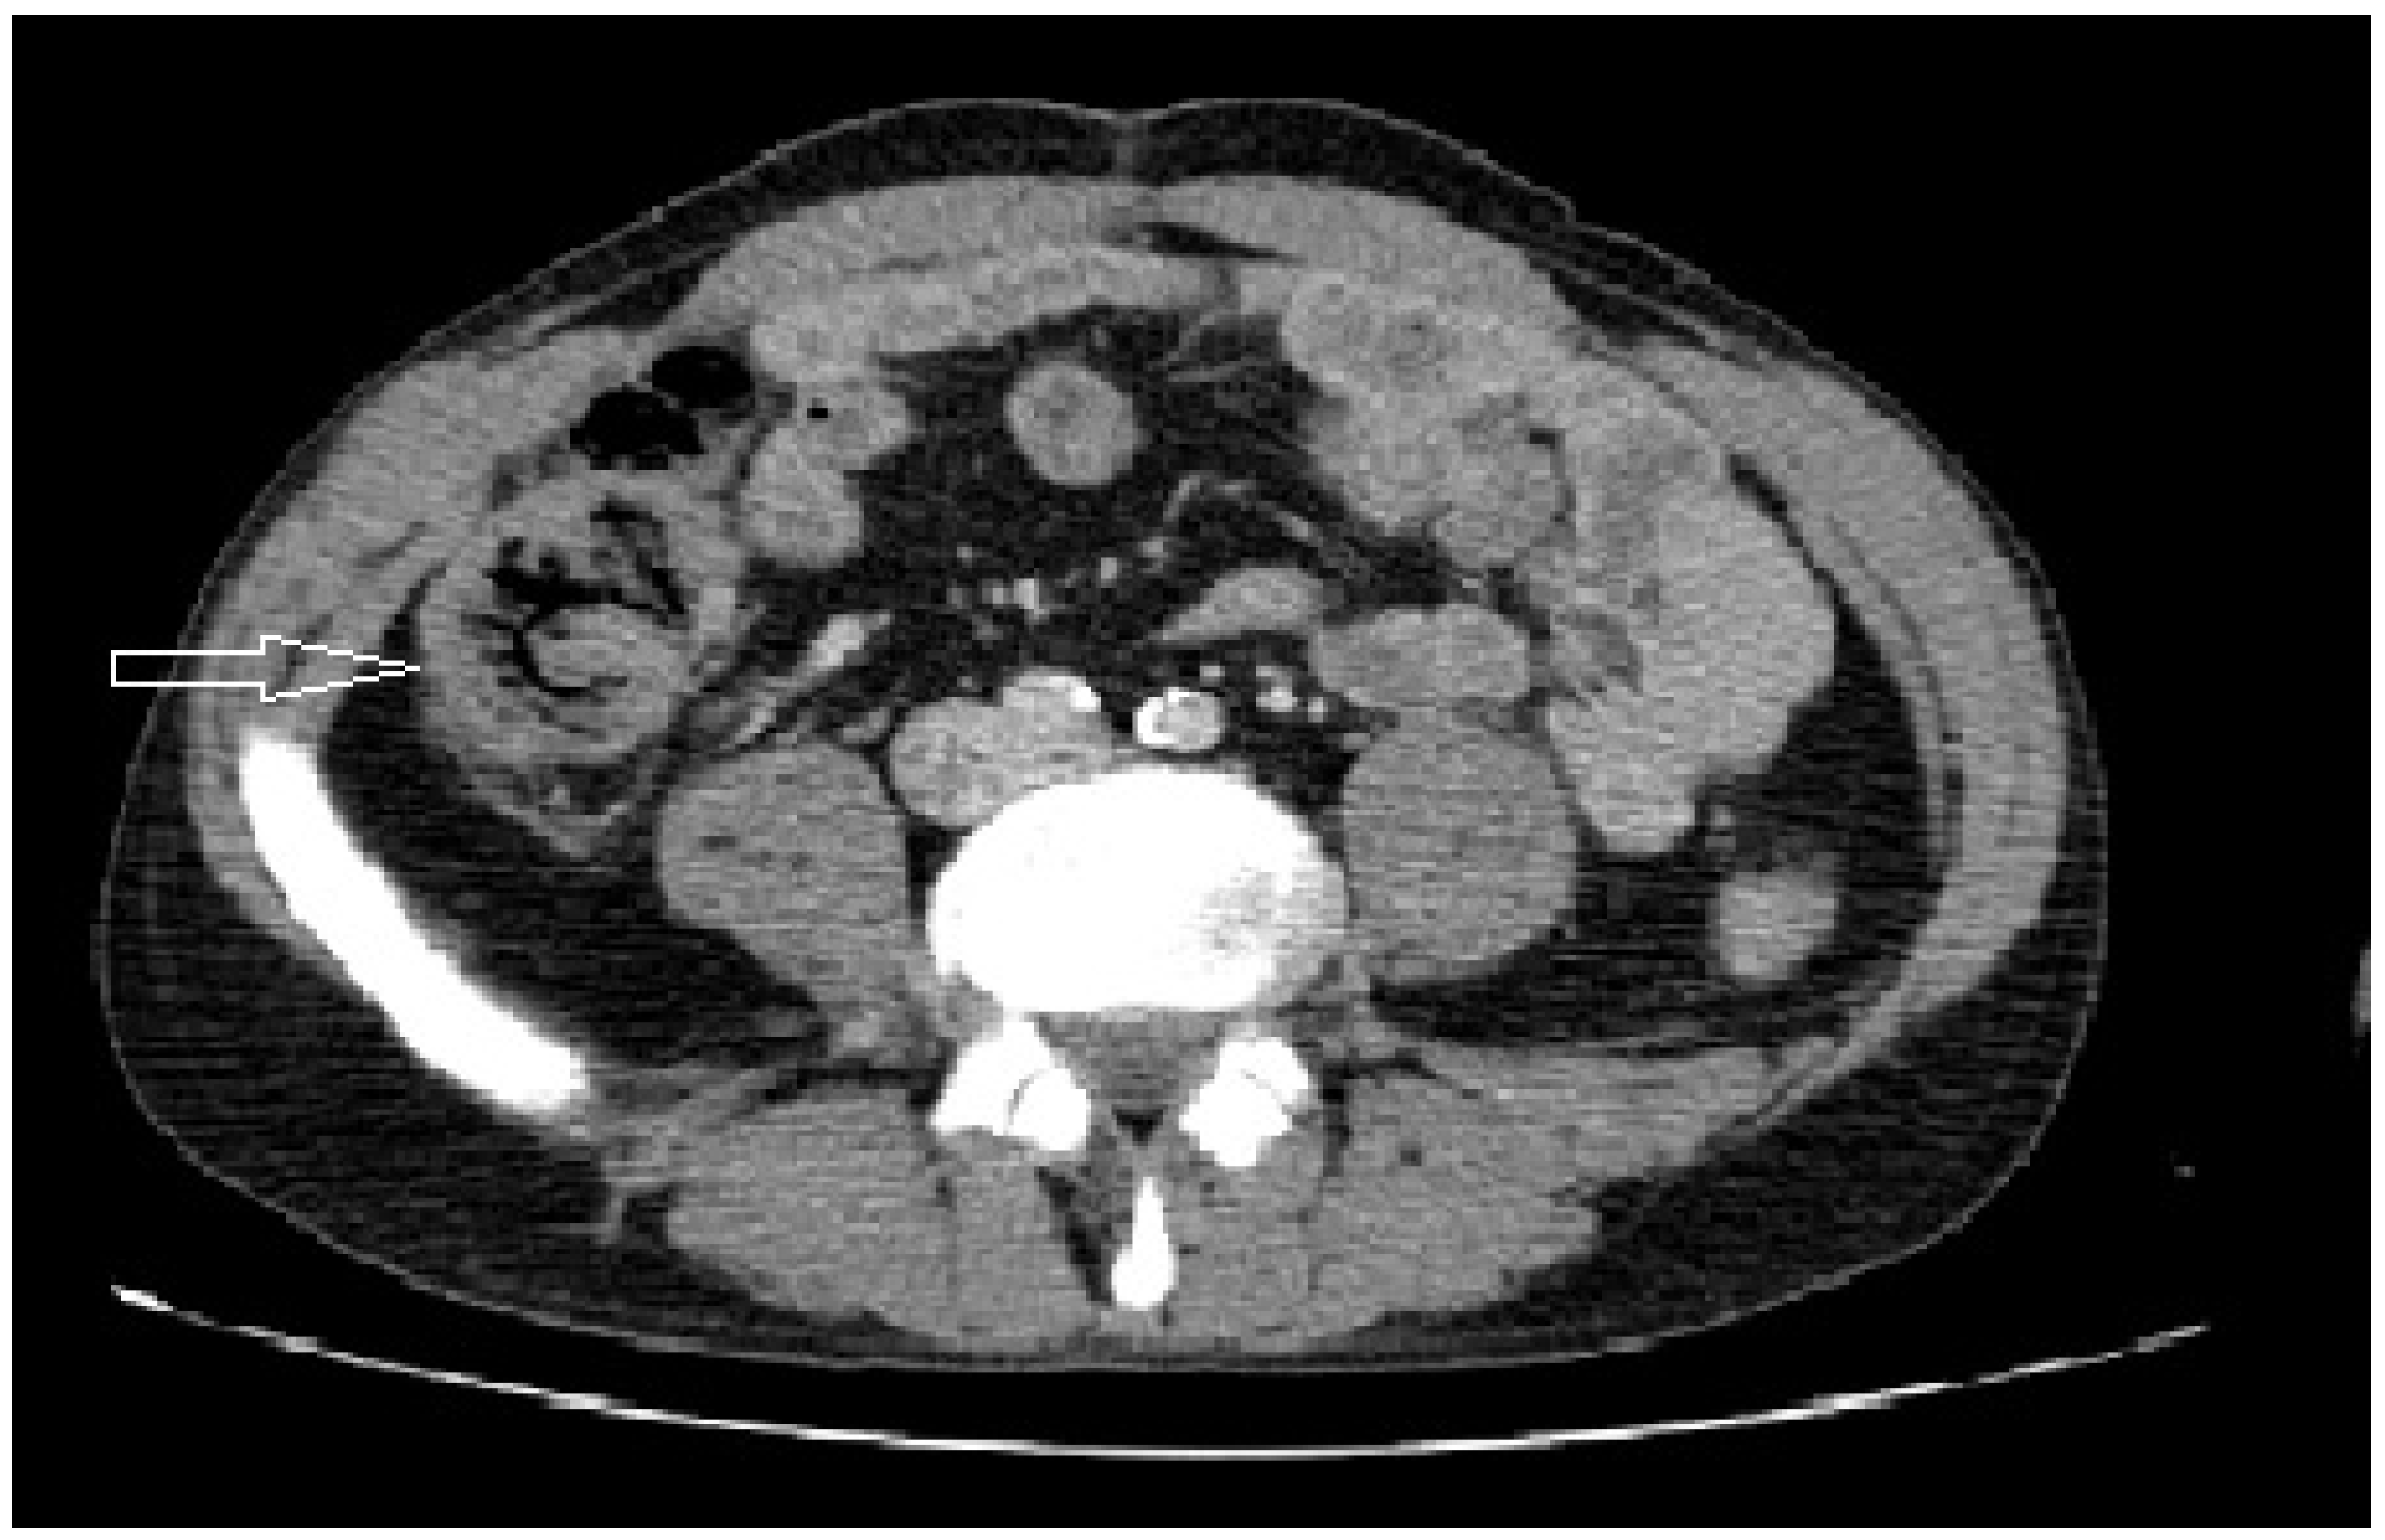

| Air in the bowel wall | 1/7 |

| Increase in thickness of the cecum wall | 2/7 |

| Perforation | 3/7 |